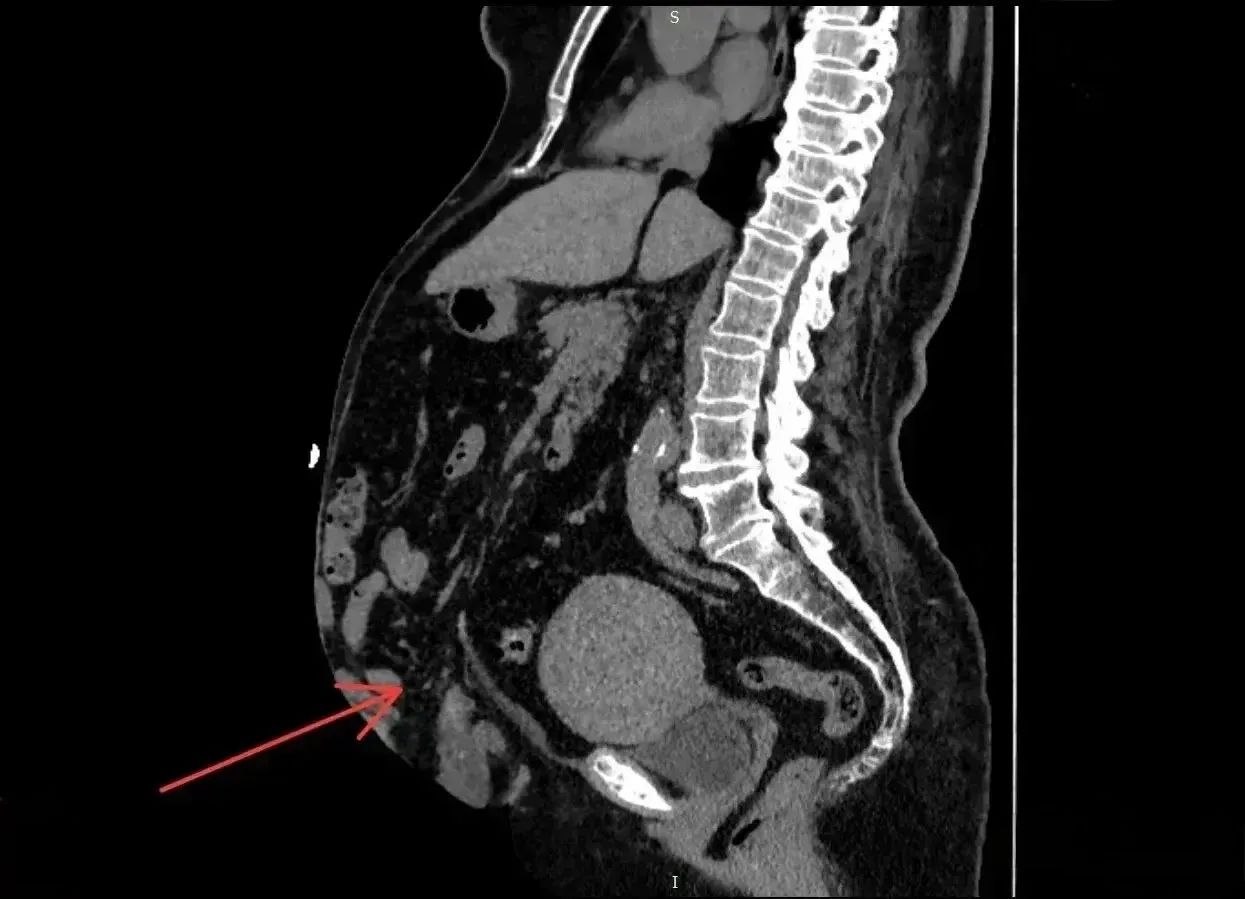

Результаты компьютерной томографии показали, что грыжа достигла 41% от объёма брюшной полости.